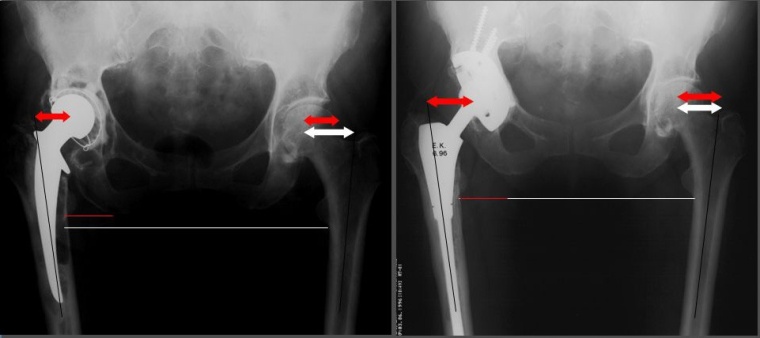

b. die Rekonstruktionsmöglichkeit der Biomechanik (Offset, Beinlänge, Anteversion) auch nach Fixierung der diaphysären Komponente.

Je nach Modellvariante können mit einem modularen System durch Rotation und Formwahl der metaphysären Komponente Offset, Beinlänge und Anteversion effektiv rekonstruiert werden. Dieses dient der Funktionsverbesserung des Gelenkes, das durch die Voreingriffe mit ohnehin schon kompromittierter Muskulatur vorgeschädigt ist (Abb. 4).